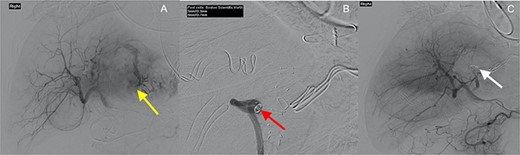

He was hypotensive (systolic 60 mmHg) with a grossly distended abdomen that was tender to palpation in all quadrants with associated guarding and localized peritonism in the right upper quadrant. A bedside ultrasound of the abdomen suggested a peri-hepatic collection. After initial resuscitation, haemodynamics improved and the decision was made to perform a computer tomography (CT) angiogram to identify a bleeding source. This confirmed a peri-hepatic collection predominantly located around the left lobe of the liver with contrast extravasation from a prominent vessel extending towards the liver capsule (Fig. 1). Resuscitation continued with the activation of a massive transfusion protocol. Prothrombin concentrate and tranexamic acid were administered to partially reverse rivaroxaban, after coagulation studies revealed an international normalized ratio (INR) of 6.7. A Child-Pugh score of 9 (Class B) was calculated, placing the patient at a 30% risk of peri-operative mortality.

Axial and coronal contrast images of abdomen (yellow arrow—haemoperitoneum, red arrow—contrast extravasation from segment II/III artery).